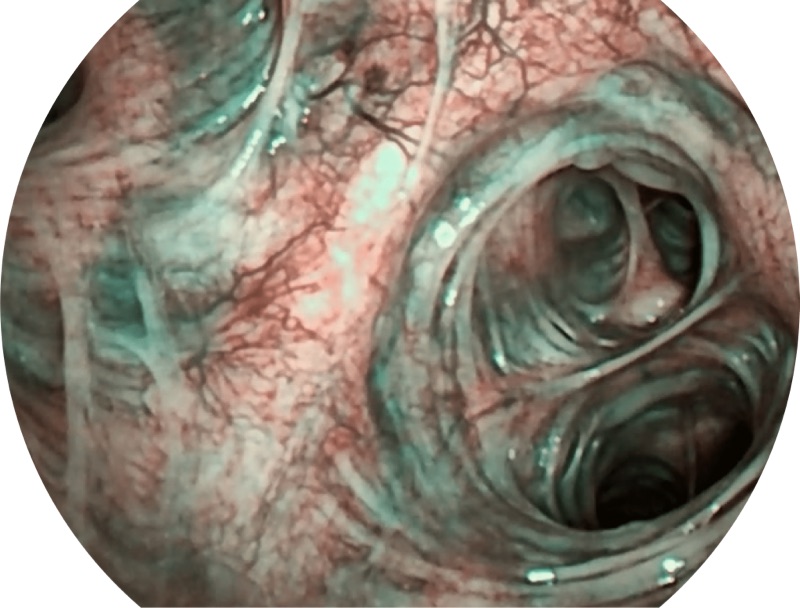

帮助医生更加清晰地观察气管表面病灶

白光

SFI

VIST